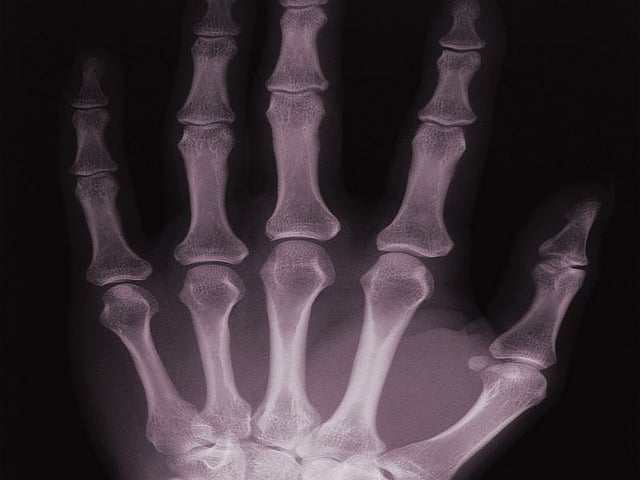

Cracking Knuckles Experiment . The pop we hear when knuckles or other joints crack involves gas bubbles within the fluid that lubricates joints. The participants were asked crack the knuckle at the base of each finger, known as the metacarpophalangeal joint (mpj), while being observed. Science student vineeth chandran suja was cracking his knuckles in class in france when he decided to investigate. The latest physical anthropology research indicates that the human evolutionary line never went through a knuckle. A new study proves once and for all the reason why cracking your knuckles makes so much. Scientists have finally gotten round to investigating what really happens when you crack your knuckles. But exactly how that air makes noise is a bit, well, up in the air.